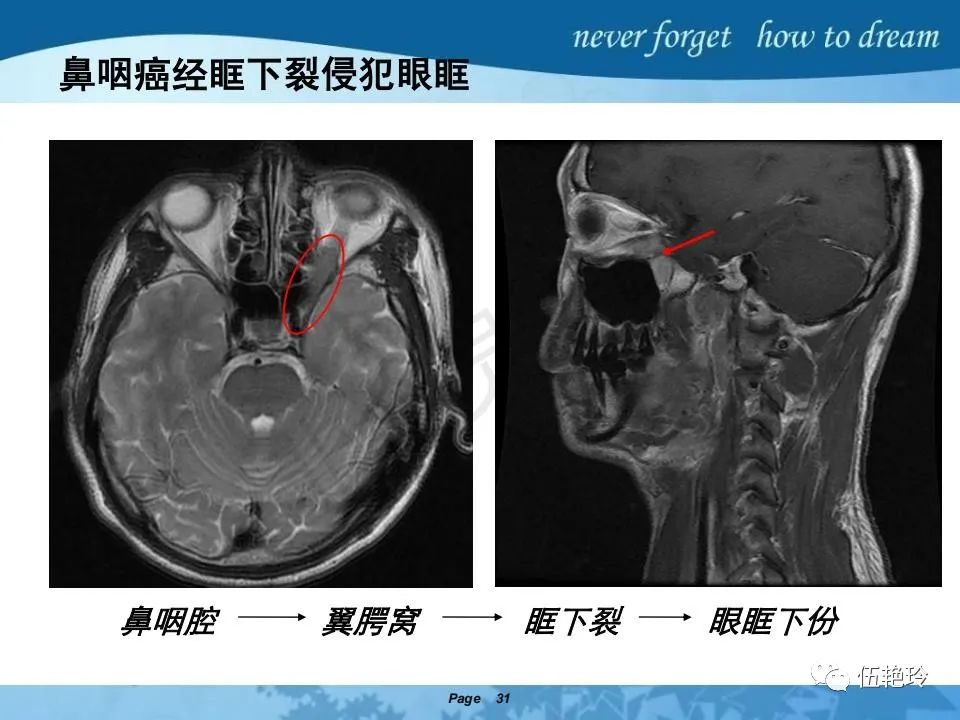

2.2 鼻咽特有的解剖途径:鼻咽癌原发灶循序进展的总途径:鼻腔(47.8%)→翼腭窝(15.2%)→ 眶下裂(3.2%)→眶尖(1.2%)→海绵窦(0.6%)。

2.31 向上颅内:①鼻咽顶壁→破裂孔(岩尖、斜坡)→蝶窦、海绵窦;②鼻咽顶壁→蝶骨基底部→蝶窦、海绵窦;③鼻咽侧壁→茎突前间隙→蝶骨大翼(卵圆孔)→海绵窦;④鼻咽侧壁→茎突前间隙→翼腭窝→ 颞下窝;⑤鼻咽前壁→鼻腔→翼突、翼腭窝→眶下裂→眶尖→海绵窦;⑥鼻咽前壁→鼻腔→上颌窦、筛窦;